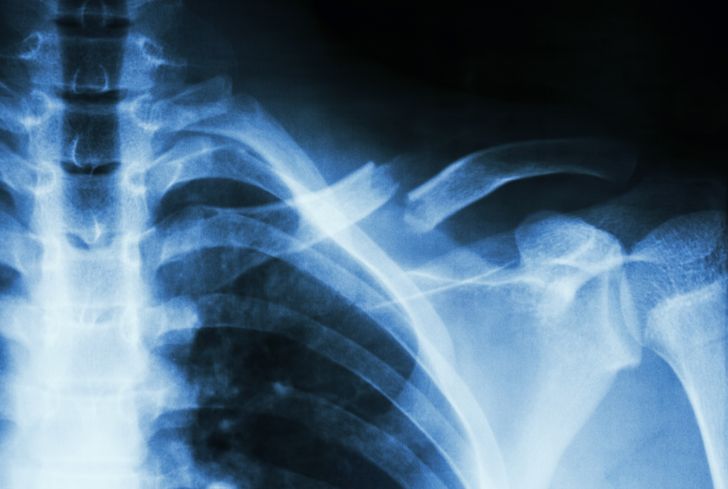

‘De vakantie! En de familiedag! Verdomme dat etentje vrijdag! Morgen mooi weer, maar dat zal geen varen worden!’ De gedachten aan een wreed onderbroken burgerbestaan werden ruw verstoord door de bestuurder van het busje, die hevig geschrokken tegen me begon te tieren: ‘WAT DE FOK DOE JIJ NOU MAN!?’ herhaalde de Marokkaanse jongeman een paar keer. ‘Nou moe, je kan ook eerst ff vragen hoe het met mij gaat,’ mompelde ik versuft. Ik was opgestaan en weer gaan zitten. Vol verbazing keek ik naar het stuk bot dat – gelukkig onderhuids – in een rare hoek vanuit mijn schouder omhoog wees.

De Marokkaanse jongen kwam zelf tot dat inzicht en vroeg plotseling met een verschrikt gezicht hoe het eigenlijk met mij ging. ‘Het gaat, het gaat,’ mompelde ik en zei: ‘Sorry dat ik je zo liet schrikken.’ Zijn antwoord ontging me, ik werd afgeleid door een man die achter me stond en ‘Ja, rotkruising hè?’ zei, op een toon alsof we er eens lekker over zouden gaan converseren. Ik hobbelde naar de stoep, draaide terug om want ik wilde mijn fiets pakken en op dat moment kwam er een andere man die me sommeerde te gaan zitten. Hij zette zelf de fiets opzij, kwam voor me zitten en stelde zich voor. ‘Ik ben BHV’er,’ begon hij. ‘Kun je me vertellen wat er gebeurd is?’ Zijn ontspannen, vriendelijke voorkomen bracht me terug op aarde. Ik kon het tot in detail navertellen en voelde enorme opluchting dat ik kennelijk nergens met m’n kop tegenaan geknald was. ‘Alleen m’n schouder...’ De man belde mijn vrouw. De ambulance kwam voorrijden. M’n sleutelbeen is volledig aan gort. Gesneuveld op de voorruit van het busje van een slotenmaker.